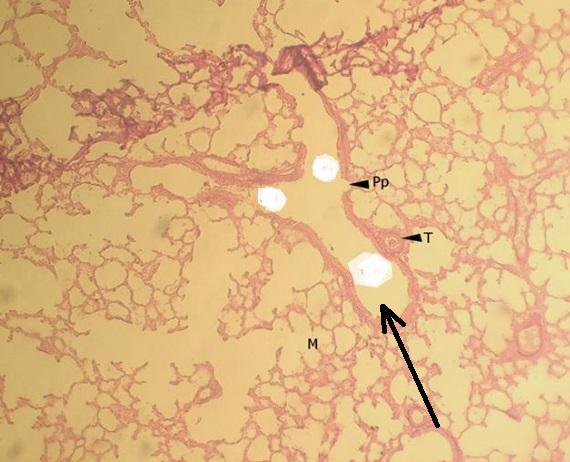

Pytanie 591

oskrzelik końcowy (płuco, barwienie fuksyną paraaldehydową)